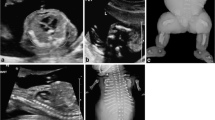

Total fetal lung volume (TFLV) measurement. a T2 HASTE axial image showing the lung segmentation methods tracing the region of interest (green) around the left and right lung on each MRI slice. b 3D volume rendering reconstruction of the TFLV, obtained by summing each slice area, multiplied by the slice thickness

Liver-to-thoracic volume ratio (LiTR) calculation. a T2 HASTE sagittal image shows the line drawn at the xiphoid process (continuous line) for the first plane of measurement of the LiTR, and another line indicates a plane higher in the thorax at the liver top (dotted line). b T2 HASTE image in the axial plane shows the delineation of the liver (continuous line) and the thoracic cavity (dashed line). The LiTR is obtained by dividing the herniated liver volume by the total chest volume

Percentage of liver herniation measurement (%LH). a T1 WIBE image in a sagittal view shows the liver segmentation methods with liver area measured on each slice (green) to obtain the 3D fetal level volume. b In both images, the white line drawn at the xiphoid process indicates the position of the diaphragm. The liver herniation percentage is then calculated by dividing the hepatic volume above the diaphragm by the entire liver volume

Mediastinal shift angle (MSA) calculation. True-Fisp axial image at the level of four-chamber view of the heart shows a sagittal midline (continuous line) drawn from the posterior face of the vertebral body to the mid of the sternum and a second line (dashed line) drawn from the same point of the vertebral body to touch the lateral wall of the right atrium tangentially